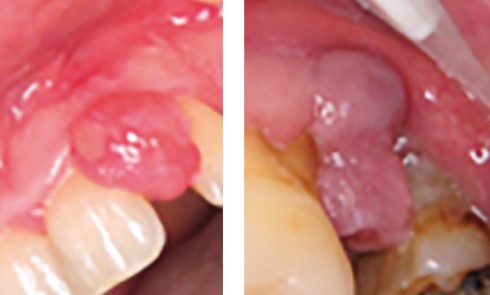

Article réservé à nos abonnés Épulis ou granulome à cellules géantes ?

CAS 1 Motif de la consultation. Patiente de 25 ans venue consulter pour l’apparition d’une tuméfaction gingivale « disgracieuse » et non...